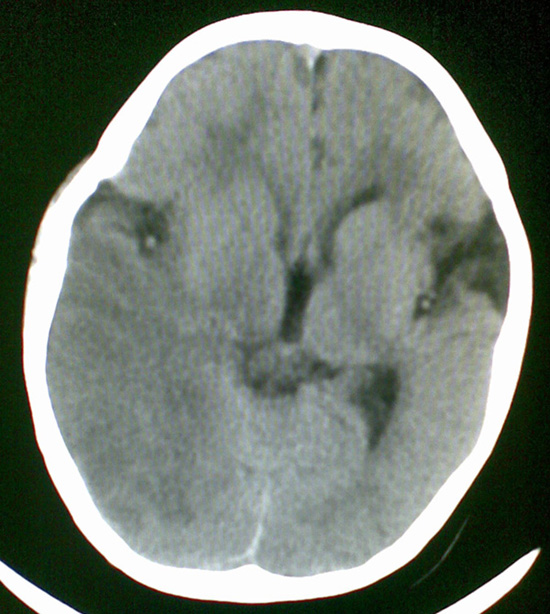

男4岁,反复抽搐多年,今早再次大抽搐,伴昏迷

1)右侧大脑半球大面积脑梗塞。2)双侧额叶脑软化灶。3)脑萎缩。

建议:必要时行dsa检查排除烟雾病可能。

1右侧大面积脑梗死2左侧额颞部软化灶。